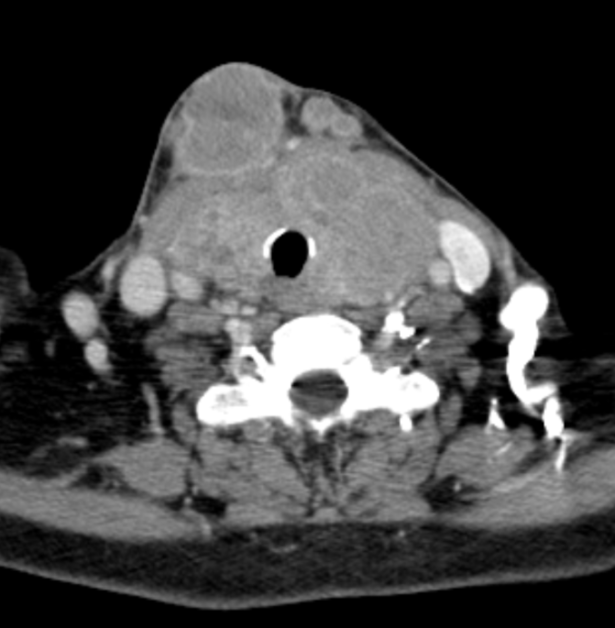

Giving Hope Through Jaw Reconstruction: Treating Ameloblastoma in Kenya

Ameloblastomas are benign but locally aggressive tumors that most often arise in the mandible (lower jaw). While they grow slowly, patients in Kenya frequently present with very large masses by the time they come for treatment — far larger than any I encountered during my surgical training in the United States. Once these tumors reach…